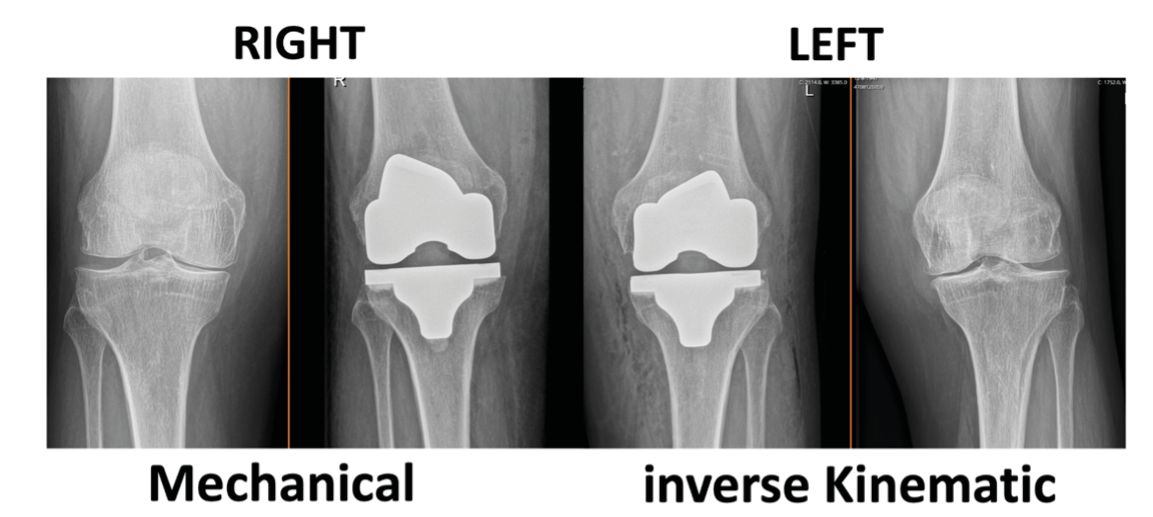

Described by Insall et al [20] Insall JN, Binazzi R, Soudry M, Mestriner LA. Total knee arthroplasty.Clin Orthop Relat Res. 1985; 192: 13-22. https://doi.org/10.1097/00003086-198501000-00003 (Figure 1) has the advantage of simplicity. In the coronal plane, perpendicular cuts are made to the tibial and femoral mechanical axes. The aim postoperatively is a straight leg (HKA 180°). Yet, MA does not consider the variability of existing morphotypes and requires soft tissue release to balance the ligament balance. It does not restore the natural varus joint line obliquity. These elements possibly contribute to the imperfect functional results [21], Karasavvidis T, Pagan C, Haddad F, Hirschmann M, Pagnano M, Vigdorchik J, Current Concepts in Alignment in Total Knee Arthroplasty, J Arthroplasty (2023), https://doi.org/10.1016/j.arth.2023.01.060. [36] V Vigdorchik JM, Wakelin EA, Koenig JA, Ponder CE, Plaskos C, DeClaire JH,Lawrence JM, Keggi JM, Impact of Component Alignment and Soft Tissue Release on 2 Year Outcomes in TKA, J Arthroplasty (2022), https://doi.org/10.1016/j.arth.2022.04.042..

More recently, Winnock de Grave introduced the inverse kinematic alignment (iKA) as new patient specific alignment concept [39] Winnock de Grave, P., Luyckx, T., Claeys, K. et al. Higher satisfaction after total knee arthroplasty using restricted inverse kinematic alignment compared to adjusted mechanical alignment. Knee Surg Sports Traumatol Arthrosc 30, 488–499 (2022). https://doi.org/10.1007/s00167-020-06165-4. iKA favors the restoration of tibial joint line obliquity as first step (Figure 1). This is followed by resection of the posterior and distal femur bone by using the gap balancing technique to achieve ligament balance without releasing soft tissues. By resecting equal amounts of bone on the medial and lateral tibial condyle the native tibial joint line obliquity is restored (Figures 2, 3, 4). In iKA also boundaries are set to attenuate extreme morphotypes. When the target zones of iKA, rKA and MA are compared, the iKA target zones matches a higher proportion of native knee alignment, followed by rKA and MA [40] Winnock de Grave, P., Luyckx, T., Van Criekinge, T. et al. Inverse kinematic alignment accommodates native coronal knee alignment better in comparison to adjusted mechanical alignment and restricted kinematic alignment. Knee Surg Sports Traumatol Arthrosc (2023). https://doi.org/10.1007/s00167-023-07326-x. Analysis of the tibial position in iKA in the coronal plane shows a mean postoperative MPTA of 86,5°, corresponding to the native joint line obliquity [40] Winnock de Grave, P., Luyckx, T., Van Criekinge, T. et al. Inverse kinematic alignment accommodates native coronal knee alignment better in comparison to adjusted mechanical alignment and restricted kinematic alignment. Knee Surg Sports Traumatol Arthrosc (2023). https://doi.org/10.1007/s00167-023-07326-x. The femoral position with the iKA shows a mean external rotation of 2° relative to the posterior condylar axis (PCA) and 2° varus position according to the native LDFA of 86° [8], Chao TW, Geraghty L, Dimitriou P, Talbot S. Averaging rotational landmarks during total knee arthroplasty reduces component malro- tation caused by femoral asymmetry. J Orthop Surg Res 2017;12:74, http://dx.doi.org/10.1186/s13018-017-0575-2 [PMID: 28499396; PMCID: PMC5429545]. [29], Ng CK, Chen JY, Yeh JZY, Ho JPY, Merican AM, Yeo SJ. Distal femoral rotation correlates with proximal tibial joint line obliquity: a considera- tion for kinematic total knee arthroplasty. J Arthroplasty 2018;33:1936–44, http://dx.doi.org/10.1016/j.arth.2017.12.025 [Epub 2017 Dec 28. PMID: 29395720]. [39] Winnock de Grave, P., Luyckx, T., Claeys, K. et al. Higher satisfaction after total knee arthroplasty using restricted inverse kinematic alignment compared to adjusted mechanical alignment. Knee Surg Sports Traumatol Arthrosc 30, 488–499 (2022). https://doi.org/10.1007/s00167-020-06165-4. Whereby, when using off the shelf implants, this varus orientation of the trochlear groove leads to an optimal patellofemoral tracking [36] V Vigdorchik JM, Wakelin EA, Koenig JA, Ponder CE, Plaskos C, DeClaire JH,Lawrence JM, Keggi JM, Impact of Component Alignment and Soft Tissue Release on 2 Year Outcomes in TKA, J Arthroplasty (2022), https://doi.org/10.1016/j.arth.2022.04.042.. A clinical study comparing iKA with MA at 12 months follow up shows that higher proportions of iKA knees are satisfied and higher proportion of iKA knees that reach the patient accepted symptom state (PASS) thresholds for the Oxford Knee Score (OKS) [39] Winnock de Grave, P., Luyckx, T., Claeys, K. et al. Higher satisfaction after total knee arthroplasty using restricted inverse kinematic alignment compared to adjusted mechanical alignment. Knee Surg Sports Traumatol Arthrosc 30, 488–499 (2022). https://doi.org/10.1007/s00167-020-06165-4.